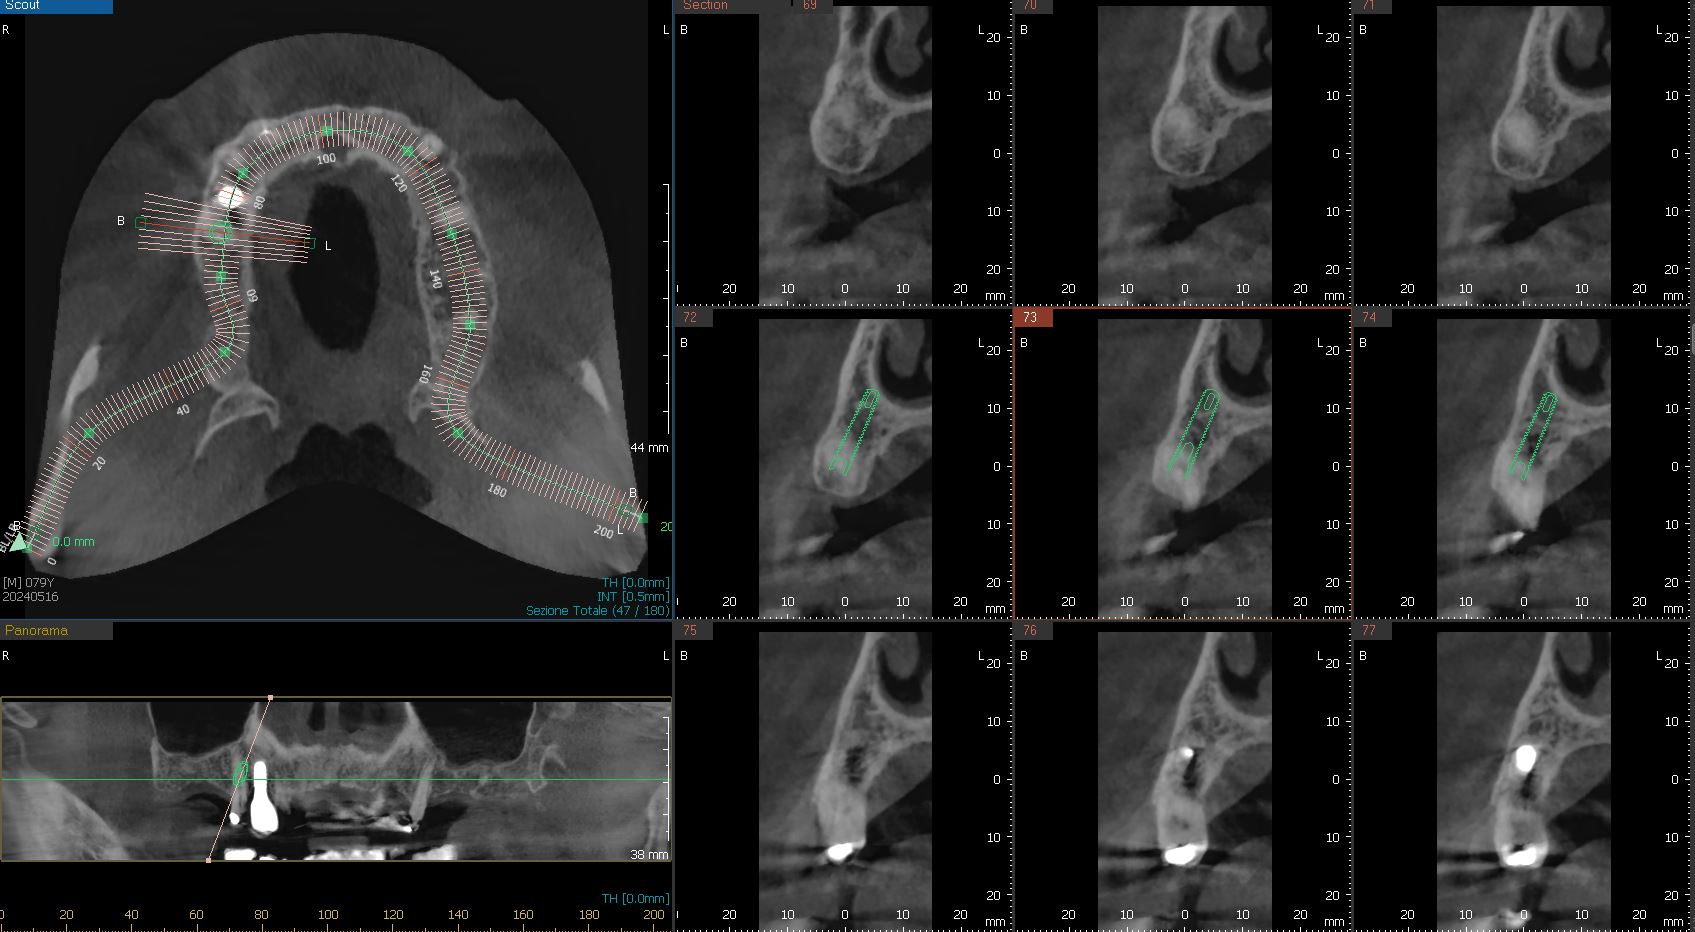

La prima fase prevede una TAC o una scansione CBCT (Cone Beam Computed Tomography) 3D della bocca e delle strutture ossee del paziente. Questi dati sono fondamentali per valutare la qualità e la densità dell’osso, oltre alla posizione di eventuali nervi o cavità sinusali.

La seconda fase prevede un’impronta con una scansione ottica (che sostituisce le impronte tradizionali) per mettere in relazione il quadro radiografico con quello clinico. (Queste informazioni consentono di capire se la procedura a carico immediato è possibile, poiché richiede una quantità sufficiente di osso per sostenere gli impianti).

2. Pianificazione digitale avanzata

Le immagini raccolte vengono caricate in un software di pianificazione che ricrea un modello tridimensionale della bocca del paziente. In questa fase, il dentista può definire con estrema precisione il numero e la posizione degli impianti, nonché l’orientamento, la lunghezza ed il diametro con cui dovranno essere inseriti. La pianificazione prevede anche la realizzazione della protesi provvisoria, che verrà posizionata subito dopo gli impianti.

Esempio di pianificazione dell’impianto (in verde)

Esatta corrispondenza dell’inserimento implantare

Nella proiezione tridimensionale della foto di destra si nota in alto a sinistra il posizionamento dei sei impianti nello spessore osseo, in basso a sinistra gli impianti visti in posizione frontale, sulla destra le nove sezioni ossee con l’impianto visto da proiezione laterale.